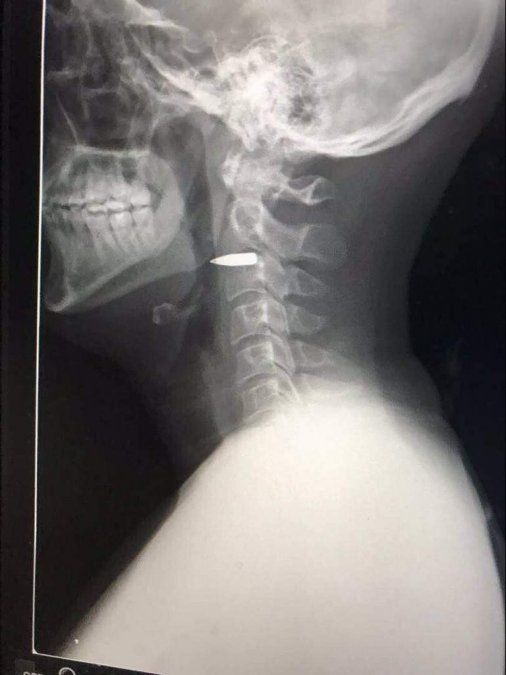

Pero no fue hasta que le realizaron una prueba de rayos X en un centro médico que se enteró de que tenía una bala en el cuello. "Estaba alojada detrás de la mandíbula" y no había alcanzado ninguna zona importante. "Es la clase de herida que duele, pero unos minutos después ya estaba bromeando con mis compañeros. Se volvió un poco más grave cuando vi la radiografía".